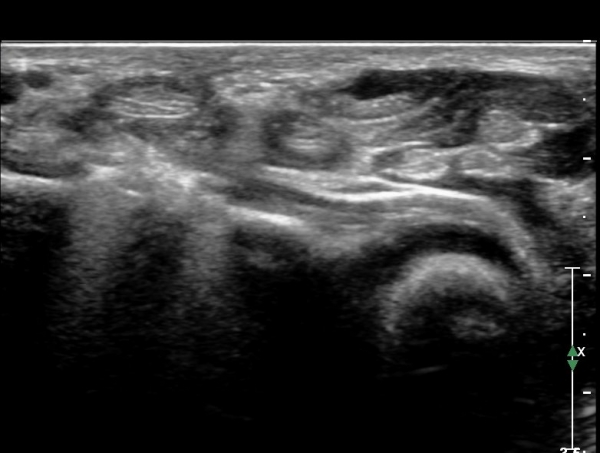

¼Õ¸ñ ºÎÀ§ Á¾´Ü¸é°Ë»ç¿¡¼­  FCR ÈûÁÙÀÌ °íÁ¤¹°°ú Á¢ÃËÇϰí ÀÖ´Â °ÍÀÌ È®Àεdzª ÈûÁÙÀº °í¿¡ÄÚ¼¶À¯È­ ¾ç»óÀ» º¸¿©

Á¤»ó ¼Ò°ßÀ¸·Î ÆÇ´ÜµÊ(»çÁø 8. 9)

Å½ÃËÀÚ¸¦ ¾à°£ ³»ÃøÀ¸·Î À̵¿ÇÏ´Ï FPL ÈûÁÙÀÌ °íÁ¤¹°¿¡ ÀÇÇØ ¾Ð¹ÚµÇ°í ÀÖÀ½ÀÌ È®ÀÎµÇ°í ±ÙÀ§ºÎ¿Í ¸»´ÜºÎ´Â

Àú¿¡Ä¿ ºÎÁ¾ÀÌ °üÂûµÇ°í ±× »çÀÌ´Â °¡´Ã¾îÁ®¼­ ÈûÁÙÀÇ ¼Ò½Ç(ÆÄ¿­)À» ÃßÁ¤ ÇÒ ¼ö ÀÖÀ½(»çÁø 10. 11)